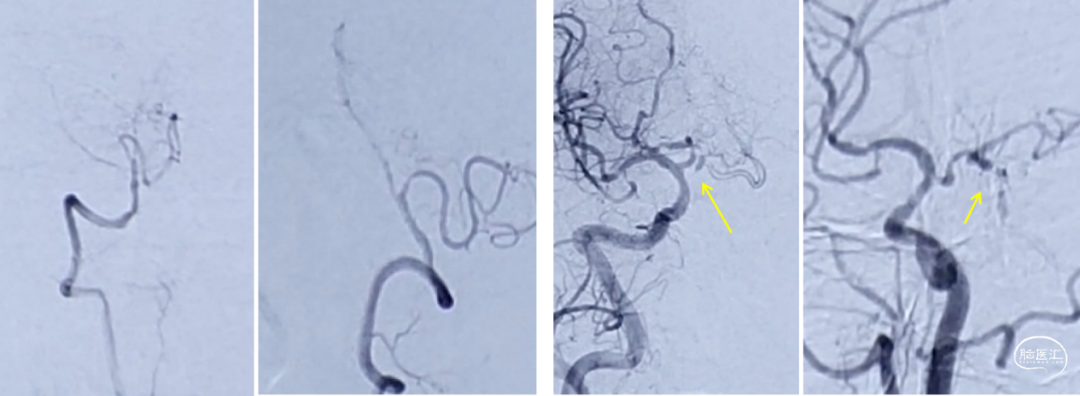

图片3

图片3显示右侧椎动脉相对劣势;发出PICA后管腔纤细;右侧后交通动脉开放,可见基底动末端及其分支显影(黄箭头)。